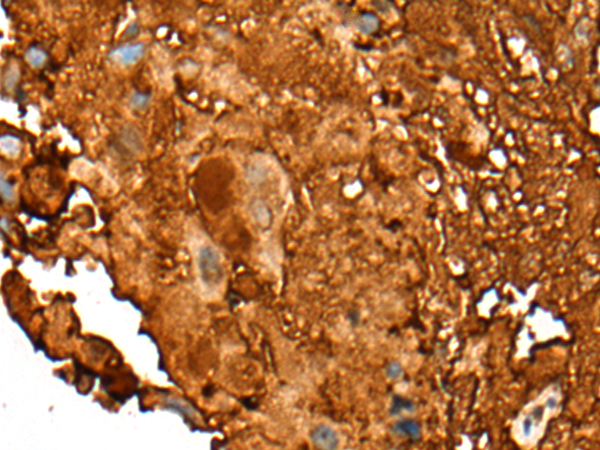

分类: 科研抗体货号: P12873别名: C35; ORB3; XTP4; RDX12; C17orf37应用: IHC反应种属: Human, Mouse